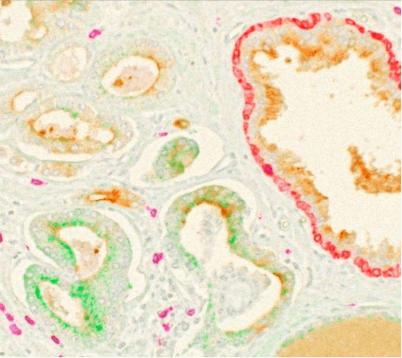

Chromogenic immunolabeling uses enzyme-conjugated secondary antibodies (horseradish peroxidase, HRP, or alkaline phosphatase, AP) to convert chromogenic substrates into colored precipitates at the site of antigen binding. Labeled tissues are visualized using transmitted light microscopy. Vector Laboratories sells a number of substrates that are oxidized by HRP or hydrolyzed by AP into different colored precipitates for multiplexing. Chromogenic methods are good for long-term slide storage, but the degree of multiplexing is limited (Figure 2). The common enzyme assay ELISA is also based on chromogenic immunolabeling with a colored, water-soluble reaction product.

Figure 2. Composite image of all 4 chromogens (PSMA, CD8, basal cell and P504S) plus hematoxylin to produce 5-color brightfield (transmittance) representation of prostate tumor FFPE tissue. Used under CC by 4 license without modification from (Morrison, 2025) Figure 6c.